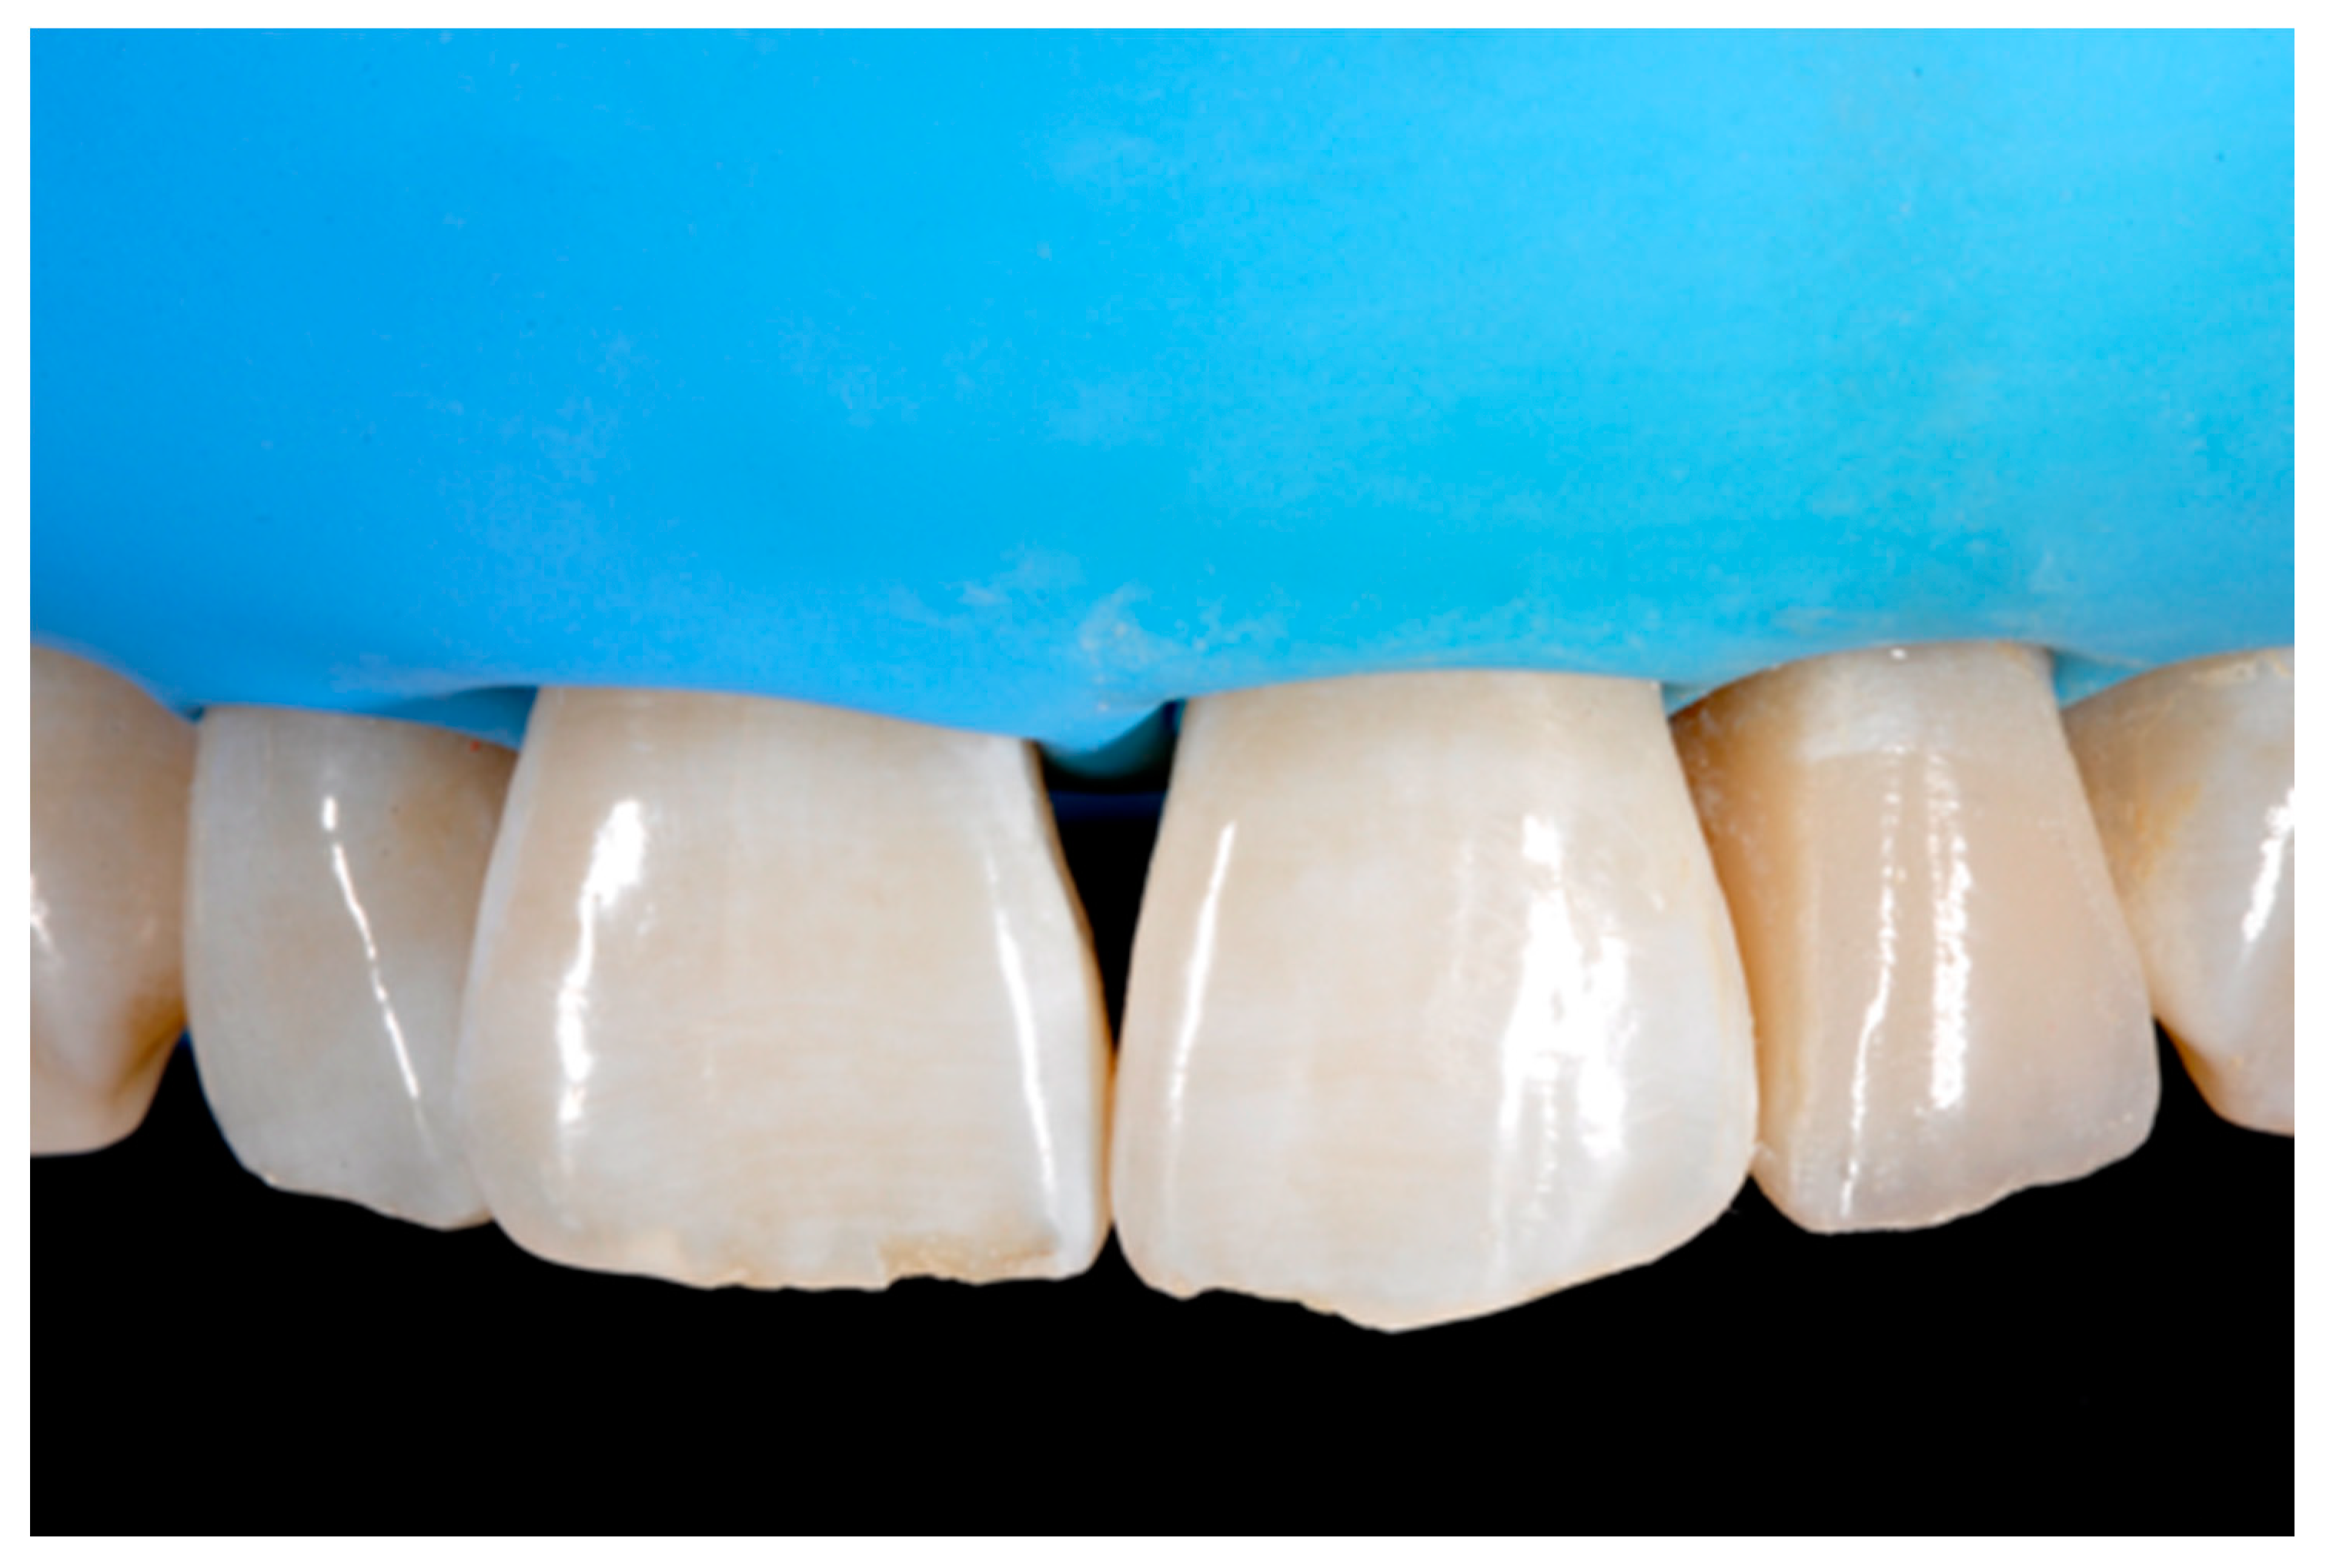

Dentistry Journal Free Full Text The Pre Finishing Approach In Direct Anterior Restorations A Case Series Html